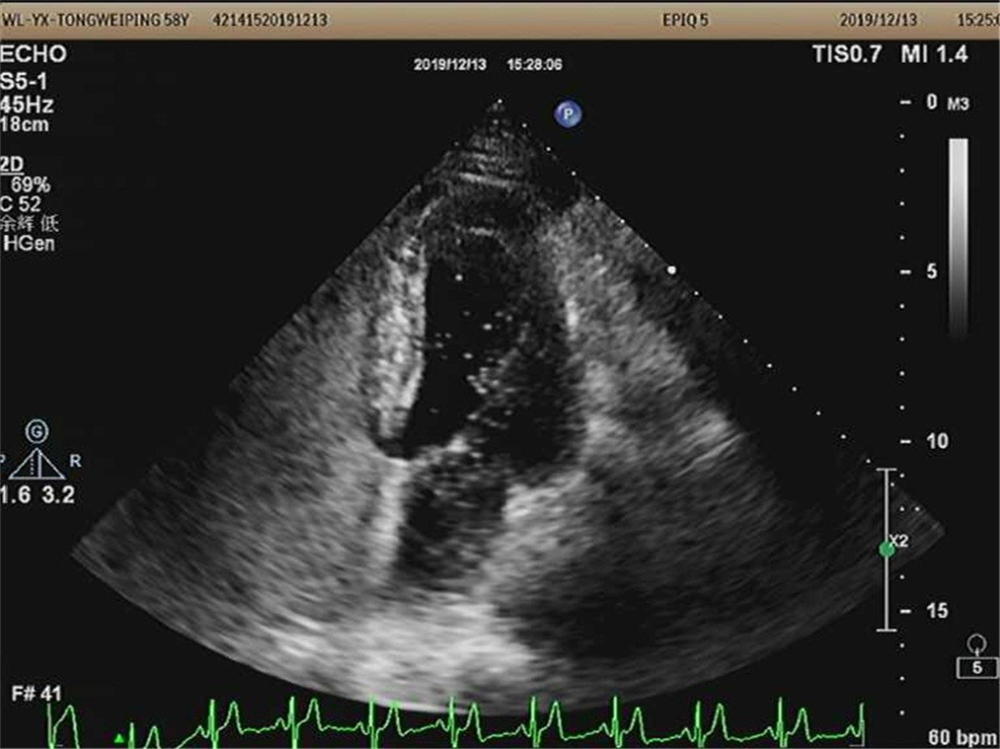

右心声学造影检查是利用微气泡造影剂经上肢浅静脉注射,造影剂气泡直径>10微米,平均15微米,正常情况下不进入左心系统,由于微泡与血液存在明显声阻抗差,即使个别微泡(低速微量血流)也能清晰显示,根据显影顺序、途径和时间对某些结构和血流异常做出诊断和鉴别诊断。

1、卵圆孔未闭:人群中卵圆孔未闭发生率25%-30%,在很长一段时间内被认为“无关紧要”,但近年研究发现它与年轻人无法解释的脑梗死或者短暂性脑缺血发作患者的相关性较高,偏头痛与卵圆孔未闭也有显著关联,尤其是视觉异常等先兆症状、反复发作者。